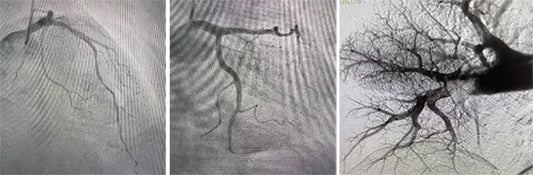

Beijing Anzhen Hospital has achieved another milestone in integrated cardiovascular and pulmonary care. The hospital’s Pulmonary Vascular Disease Center successfully performed a “one-stop interventional therapy” combining pulmonary artery thrombectomy and...